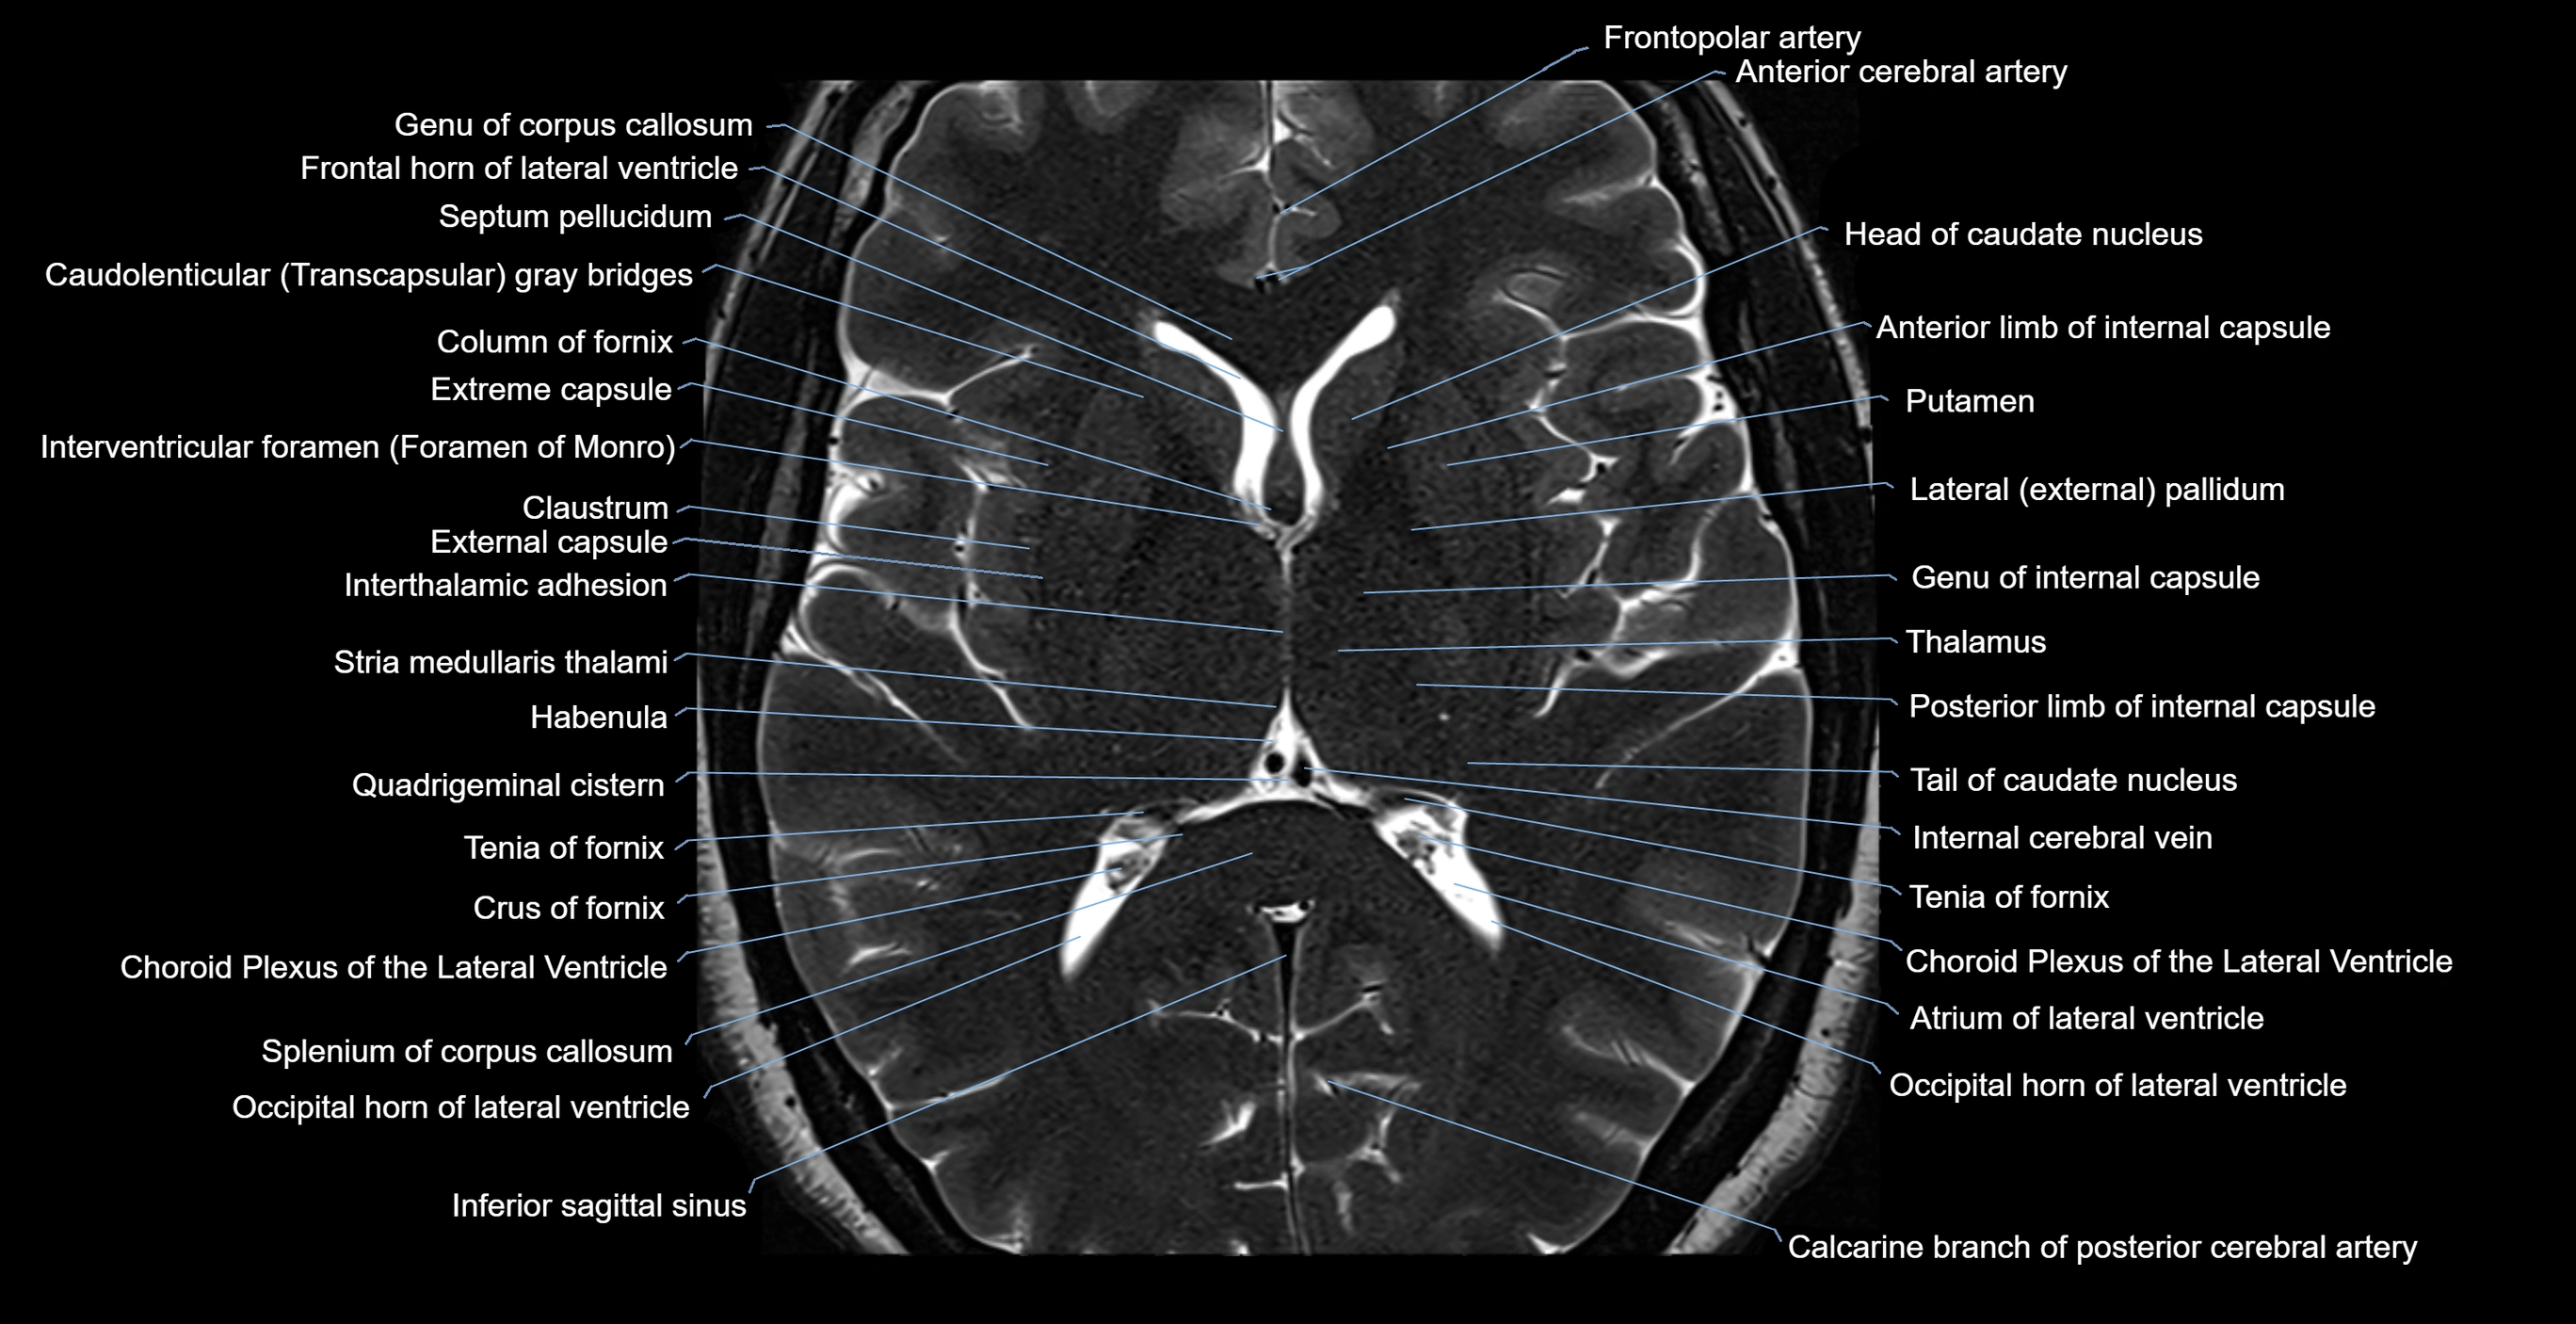

MRI images